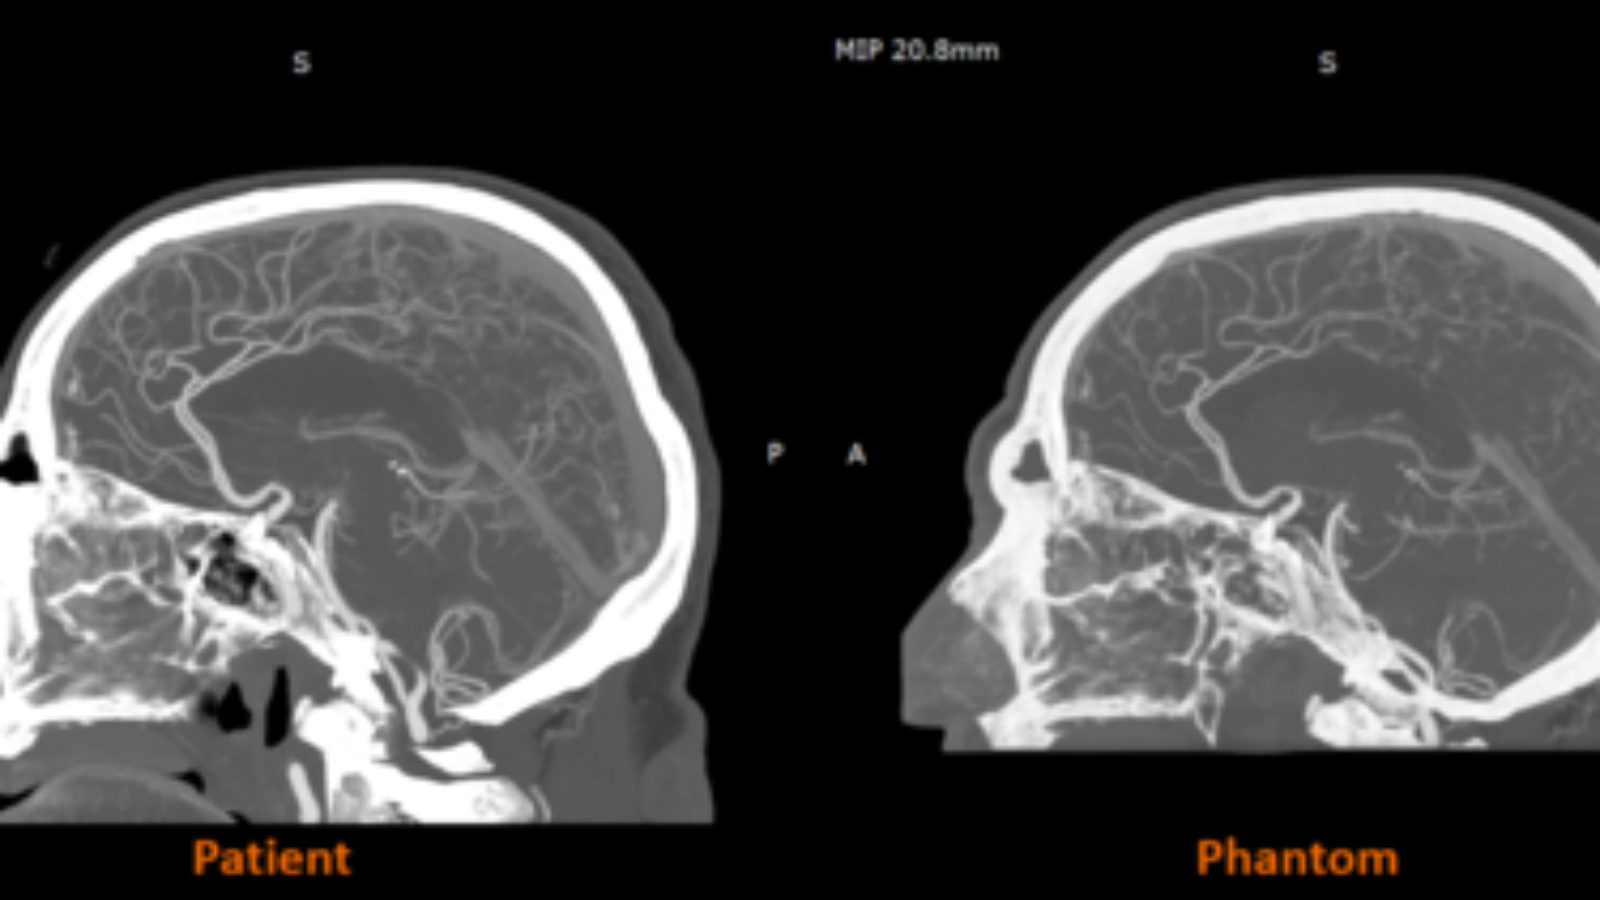

The material has already been utilized in collaborative research projects in the UK with partners including CPI and Beaumont Hospital, demonstrating its potential in clinical and educational settings. Radiopaque 3D printed phantoms, such as cerebral angiography models, are helping improve training fidelity and create repeatable environments for imaging research.

Early findings from the Stratasys–Siemens Healthineers collaboration show that RadioMatrix phantoms can replicate human tissue with high accuracy in CT imaging, with deviations as small as a single Hounsfield unit (HU) in sensitive areas like grey matter and veins. Combining Stratasys’ Digital Anatomy technology with advanced imaging algorithms, the resulting models maintain anatomical and pathological details while providing a consistent, ethical alternative to cadaver-based training.